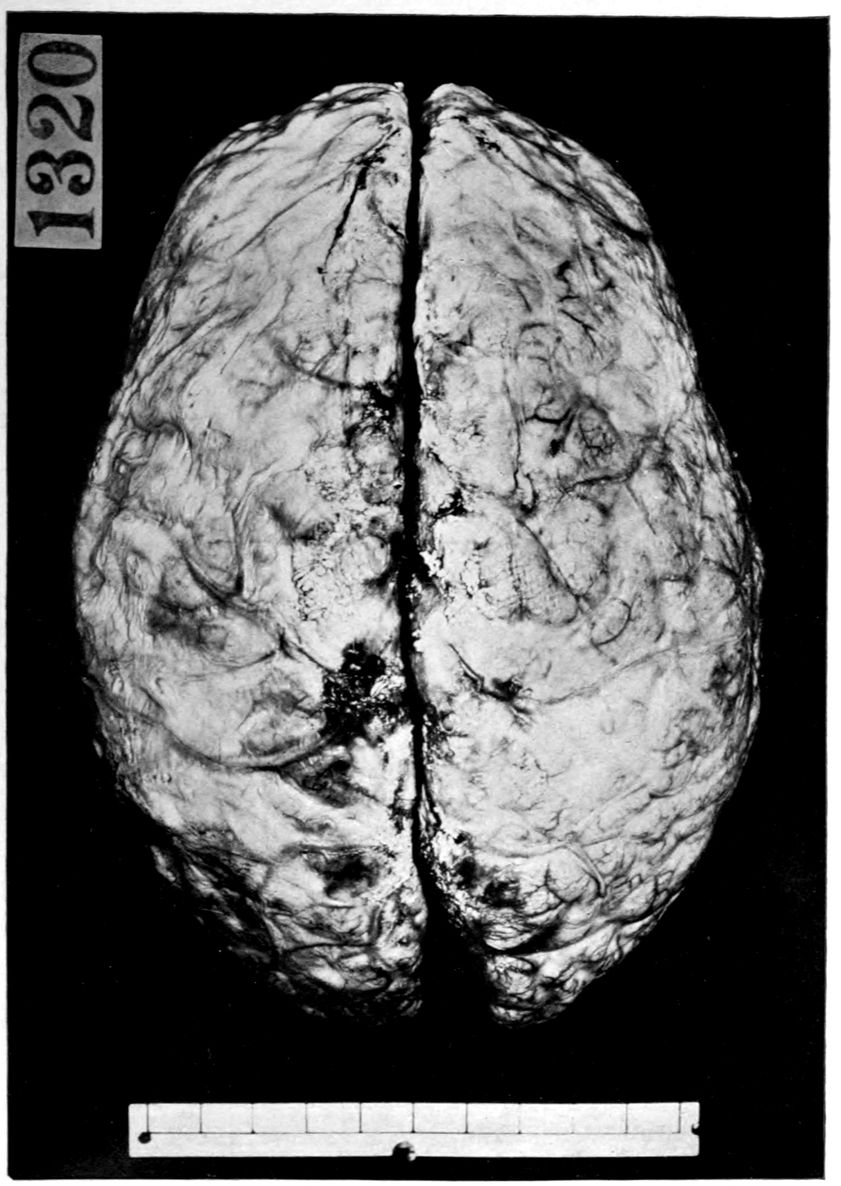

Case 4. James Pierce was an almshouse transfer to the Danvers Hospital in his fiftieth year. He died three years later. The accompanying brain pictures demonstrate so extensive a lesion of the left hemisphere that it is of great interest to determine if possible the genesis and course of his disease. It appears that syphilis had been acquired somewhere about the age of 38 or 40, so that the total duration of the process was between 13 and 15 years. In Pierce’s forty-third or forty-fourth year, he had a shock while walking in the streets of his native city, whereupon he was subsequently transferred to the Danvers Hospital, whose data have been summed up as follows (we are obliged to Dr. Charles T. Ryder for these data):

Vascular neurosyphilis—effects of syphilitic thrombosis of Sylvian artery 10 years before death. (Case 4.)